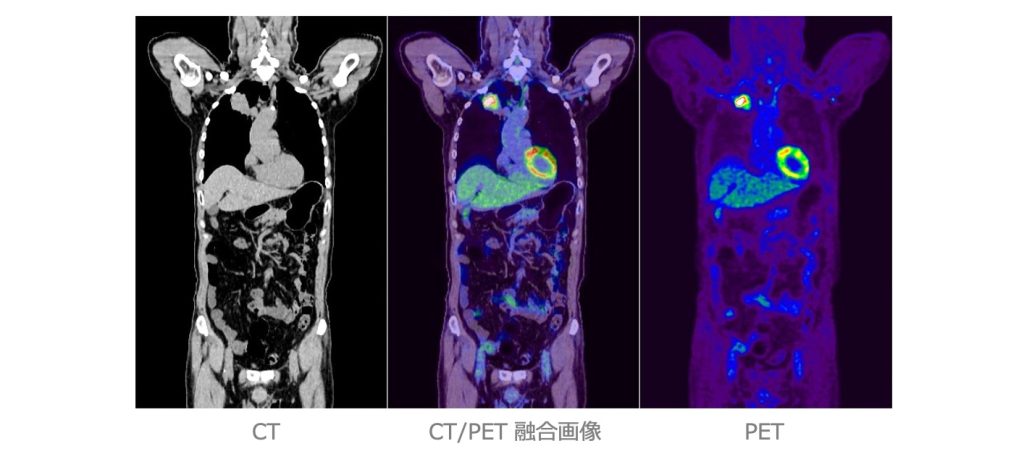

核医学検査(RI 検査)

放射性同位元素(Radio Isotope:RI )を用いた検査のことで、目的とする臓器や腫瘍に集まる薬にRIで目印を付けて投与し、放出される放射線(ガンマ線)を専用のカメラで計測します。 核医学検査はSPECT(スペクト)とPET(ペット)に分けられ、さらに心臓、脳、肺、骨、腫瘍など検査目的によって多くの検査に分けられます。

●PET/CT検査

⼀⽅、X線CT は⾝体の外からX線をあて、X線の影、すなわち臓器の「かたち」を画像化する検査です。PET/CT装置はPETとX線CTの複合機で、両者を組み合わせた情報が得られます。